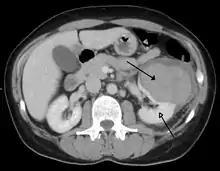

| Abdominal trauma resulting in a right kidney contusion (open arrow) and blood surrounding the kidney (closed arrow) as seen on CT | |

The kidneys may also be injured; they are somewhat but not completely protected by the ribs.[6] Kidney lacerations and contusions may also occur.[13] Kidney injury, a common finding in children with blunt abdominal trauma, may be associated with bloody urine.[13] Kidney lacerations may be associated with urinoma or leakage of urine into the abdomen.[4] A shattered kidney is one with multiple lacerations and an associated fragmentation of the kidney tissue.[4]